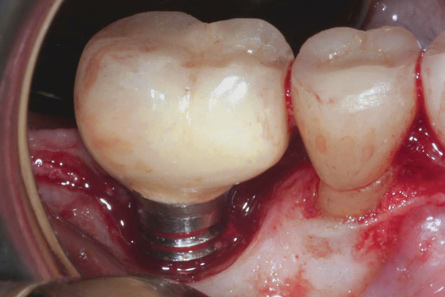

The emergence profile of implant-supported restorations through the soft tissues can be significantly different than that of natural teeth. The root of a natural tooth tends to gradually broaden as it meets the cementoenamel junction. Even with tapered and wide-diameter implants, the transition of implant to crown can appear abrupt. When a large crown is supported by a single implant, the prosthetic design may resemble that of a "lollipop," with the crown representing the candy and the implant being the stick. Molar sites are particularly vulnerable to this effect. Despite molars having multiple roots, often a single implant is used to support a single molar crown. The repercussions of this design may be undesirable (Figure 5).

Fig 5. Emergence profile of this abutment and crown created a less-than-ideal prosthetic design similar to that of a “lollipop” on a stick.

Figure 5